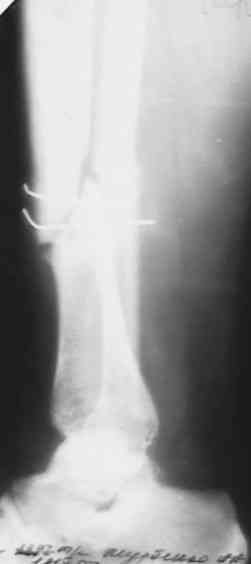

Несращение голени

поступил больной с замедленной консолидацией перелома голени . Травма ДТП 15 мая 2007года (6 мес. Назад) . Первичный диагноз : открытый перелом голени 2 А степени (Каплан-Маркова) . В одной из районных больниц выполнена трансфиксация , я так понимаю , по Паппу спицами и наложена гипсовая повязка . .Затем больной находился под наблюдением травматолога поликлиники , Свищей , длительно незаживающих ран , вроде (со слов больного) не было . ВТЭК, 2 группа . Но больной хочет ходить , (вроде нормальное желание ) На сегодняшний день имеем вот такую картинку (см. . Снимки) Анализы абсолютно нормальные . Температура 36,6 в течении суток . Клинически : отёк голени , движения в КС и голеностопном суставе практически в полном объёме . В зоне перелома определяется безболезненная подвижность , опора на конечность невозможна . PLS !!!подскажите , тактику лечения!Мой план : АВФ (БИОС недоступен) .Предполагаемый план операции: Проксимально стержень , дистально спица во фронтальной плоскости с учётом смещения . Парафрактурно оставляю <пустые> кольца . Открываю зону перелома и удаляю спицы . Остеотомия малоберцевой кости . Дистракция . В ране иссекаю межотломковую рубцовую ткань . Вскрываю костномозговые каналы . Восстановление длины и оси . Если получится ,то одномоментно . Если не нарвусь на гнойный очаг в области перелома , выполняю декортикацию . Возможно с применением аутотрансплантанта из крыла. Провожу репонирующие спицы ,стабилизирую АВФ . При наличии гнойного очага - то же самое + дебридмент , но без костной пластики и декортикации . Затем ,при благоприятном течении раневого процесса , ранняя нагрузка . При наличии проблем - ограничение нагрузки до санации раны , <аккордеонная техника> (по Голяховскому) . Прошу , выскажите замечания по технике и тактике лечения .С уважением Д.Б.

Мы бы убрали спицы через проколы кожи, по возможности. Затем аппаратом бы дозированно восстановили длину и ось. После этого закрыто

заштифтовали. Там по виду тугой ложный сустав, на дистракцию они обычно хорошо откликаются регенератом.

сегодня поставил аппарат , проблем не было . спицы убрал , но пришлось рубить малоберцевую из маленького разреза . Постепенно восстановлю длину и ось . как получится покажу снимки .Спасибо огромное всем коллегам ,откликнувшимся на вопрос !